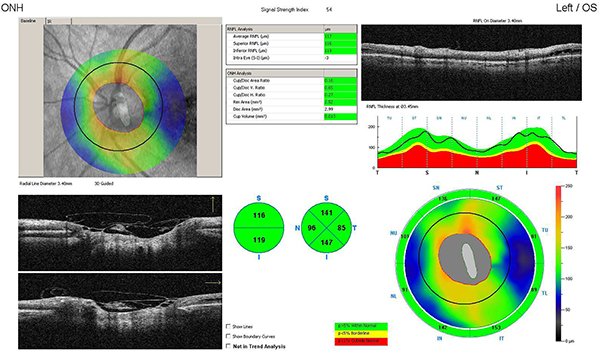

Paciente de sexo masculino de 47 años, sin antecedentes patológicos generales ni oculares de relevancia que consultó por guardia, derivado con diagnóstico de desprendimiento de retina en ojo derecho de un mes de evolución. Al ingreso presentaba una agudeza visual en ojo derecho (OD) de 5/10 sin corrección 10/10 con corrección (+1,50) y en ojo izquierdo (OI) 10/10 sin corrección. Test de Amsler alterado en OD. A la biomicroscopía ambos ojos se presentaban sin particularidades. Presión intraocular: 12/14 mmHg. Fondo de ojo derecho: papila bordes netos, excavada 0,7 atrofia peripapilar, pliegues maculares e impresionaba líquido subretinal; y en OI: papila bordes netos excavación 0,3, mácula de características normales, retina aplicada. Ante el diagnóstico presuntivo de coriorretinopatía central serosa (CCS) de OD solicitamos tomografía de coherencia óptica en donde observamos desprendimiento del neuroepitelio con compromiso de gran parte de la mácula (fig. 1). Pedimos ionograma sérico (no patológico) e iniciamos tratamiento vía oral con eplerenona 25 mg/día y tópico con bromfenac 1 gota cada 6 horas. A las dos semanas el paciente asistió a control sin mejoría de la visión (AV mejor corregida de 7/10) y sin cambios en el fondo de ojo. Realizamos nuevo OCT y vimos un aumento del líquido subretinal y retinosquisis parafoveal hacia nasal (fig. 2). Realizamos 3 inyecciones mensuales intravítreas de anti-VEGF (bevacizumab) y aumentamos la dosis de eplerenona a 50 mg/día durante 30 días, sin respuesta. A los tres meses, la AVMC era de 1/20, en el fondo de ojo, además de los pliegues maculares, observamos múltiples exudados duros maculares. Realizamos ecografía ocular a fin de descartar otras causas de desprendimiento seroso de retina y retinofluoresceinografía (RFG) en búsqueda de punto de fuga, sin hallazgos de interés (fig. 3).

Al no presentar respuesta ante los tratamientos recibidos, reinterpretamos el cuadro clínico, observando detenidamente en el fondo de ojo derecho y en OCT una lesión compatible con foseta del disco óptico con filtración de líquido hacia el espacio subretinal (figs. 4 y 5).

Los dos casos corresponden a pacientes entre la tercera y cuarta décadas de vida, que presentaron desprendimiento de retina seroso asociado a la anomalía congénita del nervio óptico no diagnosticada. Es el rango etario de presentación habitual de esta enfermedad y coincide también con la presentación frecuente de otras maculopatías1-2, 7. Una de las diferencias en las que radica el diagnóstico es que no sólo se observa desprendimiento seroso macular, sino también separación de las capas internas de la retina, y es ese patrón típico de esquisis macular que se observa en la OCT lo que nos ayudó a diferenciar la maculopatía asociada a pit de papila de otras enfermedades con líquido subretinal7-8. Por lo tanto, el diagnóstico de esta afección se basa principalmente en la observación oftalmoscópica de la foseta del nervio óptico desde edades tempranas en casos asintomáticos, pero —como ocurre en estos dos casos clínicos— los pacientes consultaron por disminución de la agudeza visual y fue necesario realizar OCT y RFG además de una observación detallada y cuidadosa de los nervios ópticos para observar los cambios típicos y descartar otras causas de desprendimiento macular seroso unilateral.